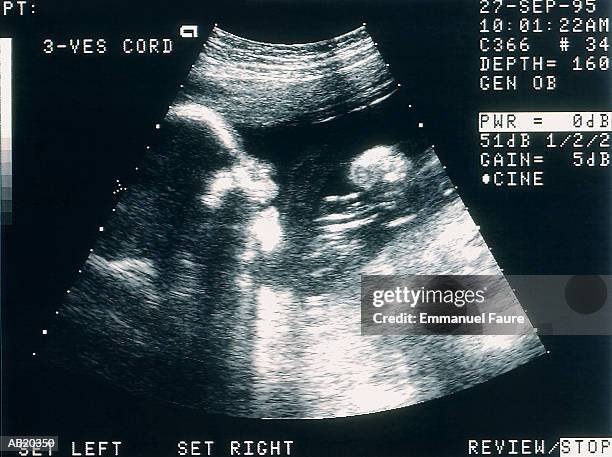

Ultra Sound

Book Appointment

DR. ANDLEEB KHALID is an experienced Consultant Gynecologist and Obstetrician with over 10 years of professional experience in the field of Gynecology and Obstetrics. She provides expert medical care both in-clinic and through online video consultations. Her areas of specialization include Antenatal Care, Antenatal Checkups, Normal And Painless Vaginal Delivery,Caesarean Section (C-Section), Postnatal Care,Clinical Breast Examination and Breast Cancer Awareness, Contraceptive Counseling, Cosmetic and Reconstructive Gynecological Surgery, Sexual Health Problems management,Diagnostic Laparoscopy, Epidural Analgesia, Gynecological Surgeries , Hysterectomy, Myomectomy , Cystectomy, Hysterosalpingogram, Hysteroscopic Procedures, Infertility Treatment, Laparoscopic Surgery, Laparotomy, Maternal and Obstetric Care, Breastfeeding Counselling, Obesity Diabetes And Hypertension in pregnancy Management, Obstetrical Ultrasound, , Tubal Ligation, Tubectomy, and UV Prolapse.